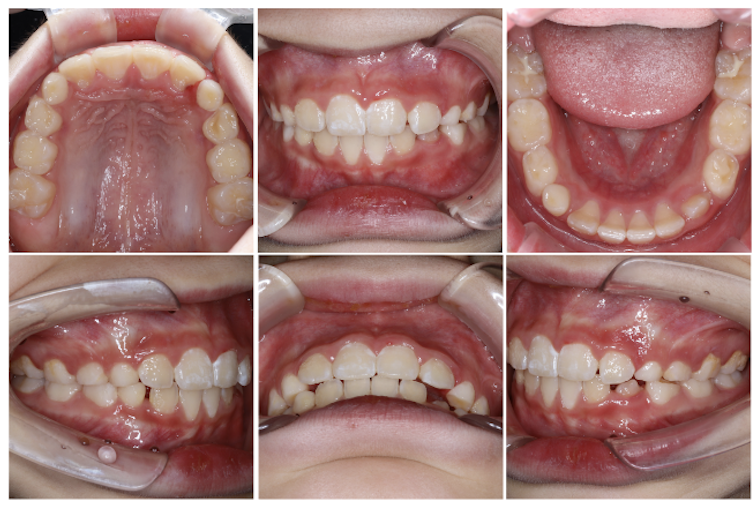

噛み合わせの深さ(オーバーバイト)は、スタートから4ヶ月で5mmから2mmの数値改善が見られました!

以降も取り組みを頑張ることで理想的な数値を維持できており、開始から1年2ヶ月経った現在の写真を見ても、噛み合わせが浅くなってきていることが分かりますね。

また、親御様が気にされていた前歯のすき間も閉じることができました。

前歯の出具合(オーバージェット)は、9ヶ月で6mmから2mmの数値改善が見られました!

現在は1.5mmまで数値改善されています。

お子様ご本人・親御様の頑張りが実を結び、素晴らしい経過となりました。